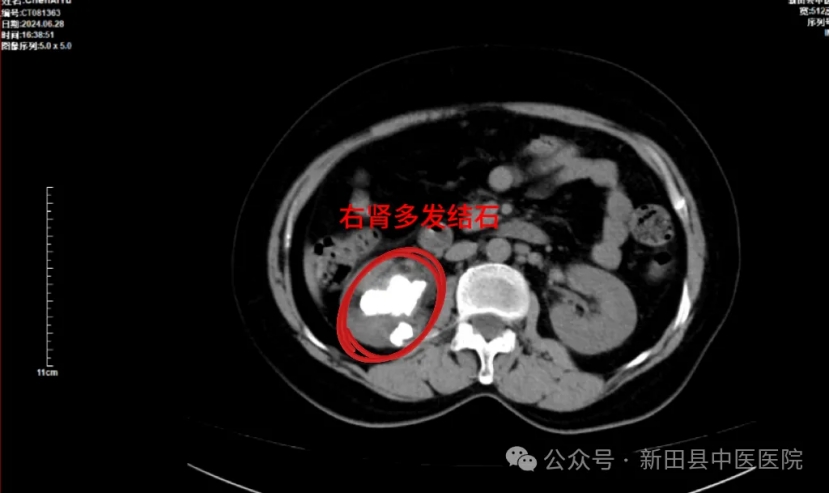

带着这些疑问,陈女士慕名到新田县中医医院找泌尿外科邓勇军主任求诊。邓勇军详细询问陈女士病史并进行了仔细体查,结合其检查报告“右肾多发结石,其中最大结石约40x27mm”,建议陈女士住院行手术治疗,并告诉她,肾脏巨大铸型结石是比较严重的,继续发展会导致肾脏积水,肾功能不全。

▲术前CT

邓勇军介绍,铸型结石是泌尿系统结石中最难处理的结石,由于患者右肾多发铸型结石大且过于分散,很难通过一次手术彻底将结石完整取出。这种结石深入到肾盂肾盏,空间比较狭小,因此碎石的时候要特别小心,既要粉碎并取出结石也要防止钬激光伤及周围组织,激光的能量控制要格外注意。同时患者肾脏完全无积水,穿刺建立通道困难且易于出血,稍有不慎则肾脏难以保全。